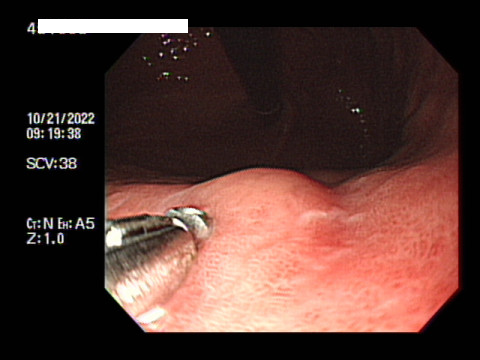

입에 재갈을 물리고 드러누워 꼼짝 못하는데 눈앞에서는 불빛을 부라리면서 곧장이라도 내 입안으로 들어올 듯한 꽃 뱀같은 내시경을 보고 있도라니 정말 너무 무서웠다.

결국엔 검사하는 내내 너무 힘들게 받았다. 뱀처럼 긴 내시경이 내 위장을 후비고 있을 때 극한의 구역질의 고통속에서 스스로 이렇게 누워있는 내 자신이 참 딱하게 느껴졌다. 이런 검사를 받고있는 것도 기가막힌데.. 힘들게 받고 있자니. 서글프다.